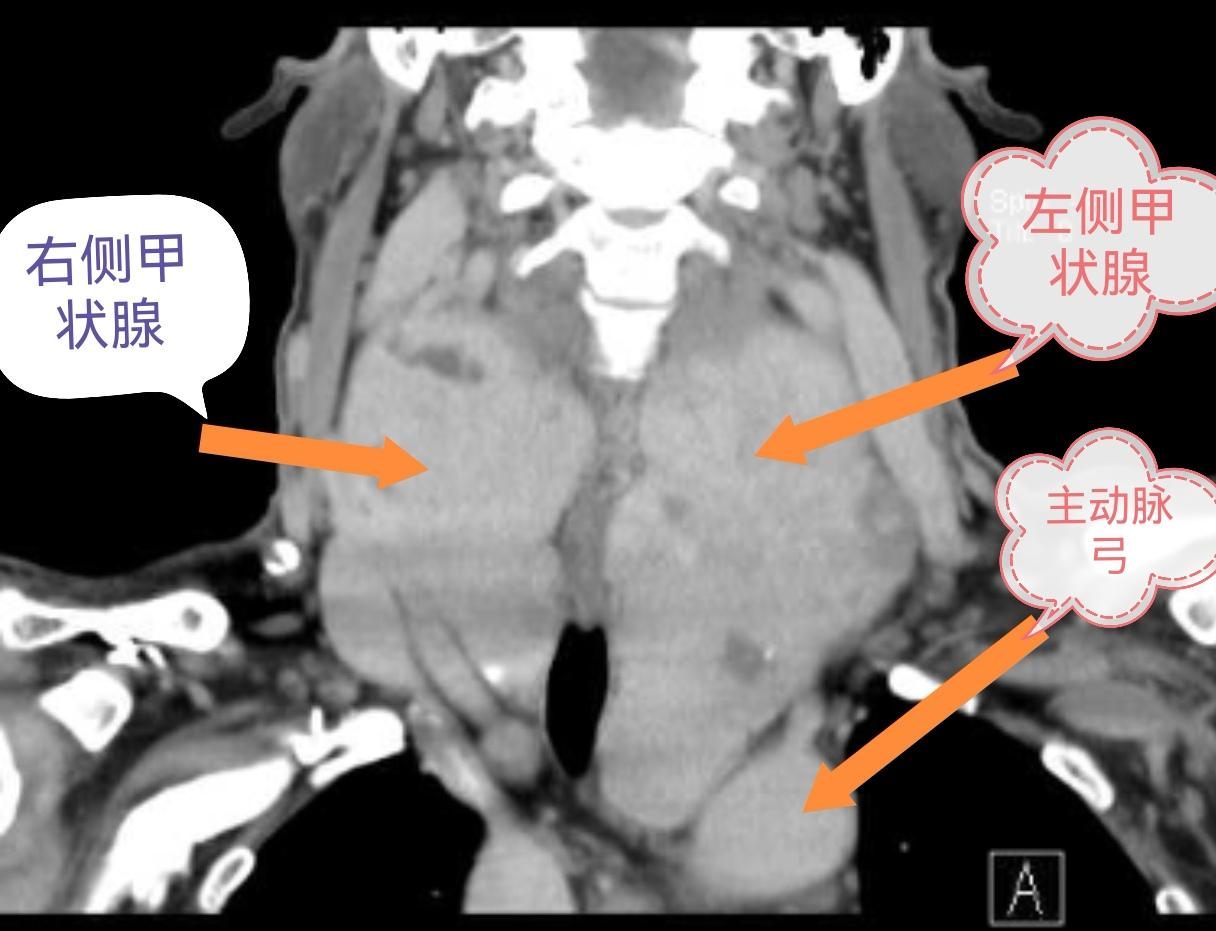

据了解,邓先生一年前发现颈部膨隆,偶有吞咽梗阻感但未重视。随着肿物增大,出现“蛙颈”畸形、夜间呼吸困难(需垫高枕头)、进食有“锁喉感”及平卧时“胸骨上窝凹陷”。增强CT显示肿物下极已达主动脉弓水平,气管被挤压变形成“细腰征”。